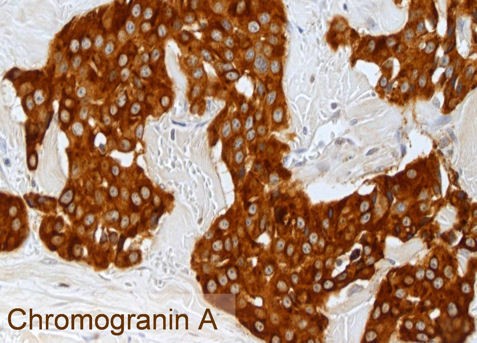

Jeder NET wird routinemäßig auf die neuroendokrinen Basismarker Chromogranin A und Synaptophysin sowie auf den Proliferationsmarker Ki-67 immunhistochemisch untersucht. Die Abbildungen zeigen einen gut differenzierten NET G2 des Ileums mit der typischen Histologie (HE = mikroskopisches Bild in Hämatoxylin-Eosin-Färbung), einer kräftigen zytoplasmatischen Färbung der Tumorzellen für Chromogranin A und einer Markierung von 12% der Tumorzellkerne für Ki-67. Der Nachweis von Chromogranin A und/oder Synaptophysin beweist das Vorliegen eines NET. Der Proliferationsmarker Ki-67 ist Grundlage für das Tumorgrading und von herausragender prognostischer Bedeutung. Deswegen muss der Pathologe dem Kliniker diesen Parameter zur weiteren Therapieplanung zur Verfügung stellen.